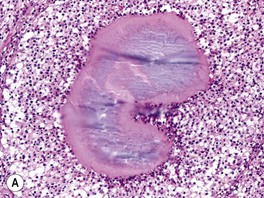

• Two subtypes: (1) actinomycotic mycetoma – secondary to filamentous bacteria, especially Nocardia and Actinomyces (see Chapter 61); and (2) eumycotic mycetoma – caused by true fungi, e.g. Madurella mycetomatis, Pseudallescheria boydii.

• Contracted from trauma and implantation of fungus into the skin (Fig. 64.17A).

Fig. 64.17 Histologic features of selected deep fungal infections. A Eumycetoma with formation of a grain, which represents tightly packed colonies of fungal organisms. B Histoplasmosis – Histoplasma capsulatum yeast forms are present within macrophages. C Blastomycosis – budding yeast forms within the dermis, several of which are within a giant cell (PAS stain). Note the single, broad-based budding (arrow). D Coccidioidomycosis – an endospore-containing spherule within a giant cell. A, Courtesy, Lorenzo Cerroni, MD; B, D, Courtesy Jennifer McNiff, MD; C, Courtesy, Mary Stone, MD.

• Most common site is the distal lower extremity but can also be seen in other sites, such as the distal upper extremity, trunk, and scalp.

• Clinical triad of draining sinuses, grains (macroscopic colonies of organisms; see Chapter 61), and edema (Fig. 64.18).